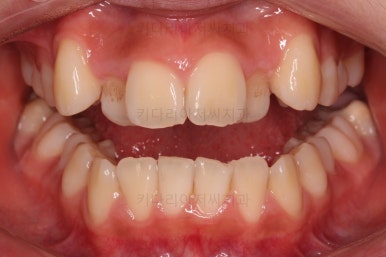

가지런하게 하면서 안으로 쏙 들어가있는 앞니를 가지런하게 할 자리 확보부터 해줍니다.

자리 확보 이 후에 가지런하게 해주는데요.

가지런하게 한 이후에는 자칫 비발치 교정이라 생길 수 있는 돌출입이라던지 뻐드러짐 등을 체크해 주고 원하시는 바와 연산동치과 의견을 종합하여 추후의 방향을 다시금 의논하게 됩니다.

약간의 뻗침과 아랫니에 비해 아주 약간 나와있는 앞니를 말씀하셨기 때문에 가능한 방법을 제시하고 치료를 이어갑니다.